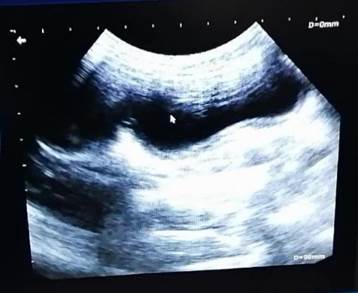

En el hemograma se observó leucocitosis de 28.8 x 103 células/µL (IDEXX VetAutoread®), mientras que en la química sanguínea se observó un aumento de las proteínas totales 11.7 mg/dL y la globulina 8.9 g/dL así como una disminución del colesterol 32 mg/dL y la alanina aminotransferasa < 10 U/L (IDEXX Catalyst One®). Para la realización del ultrasonido se hizo uso de un equipo EDAN DUS 60 VET®, (Figura 2) en el que se observó contenido anecoico abundante en el lumen de ambos cuernos uterinos y un engrosamiento de la pared uterina, descartando así la probabilidad de gestación temprana.

La vejiga se observó con distención leve y paredes de tamaño normal. Se realizó toma de muestra de orina por medio de cistocentesis ecoguiada para realización de examen general de orina (IDEXX VetLab UA®), el cual no presentó alteraciones. Con esta información, se confirmó la presencia de una piometra de cuello abierto.